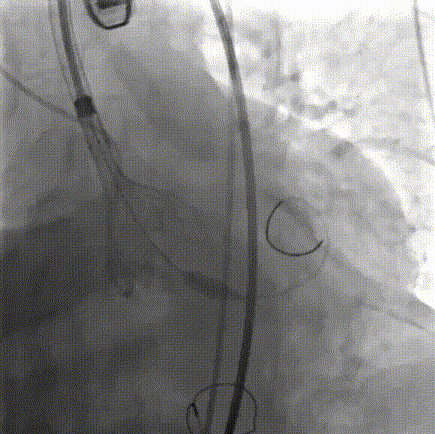

10. TaurusElite输送器顺畅过弓;

11. 造影辅助零位定位释放;

12. 第一次释放至工作位,造影、超声评估瓣膜同轴性较差;

13. 遂予以回收;

14. 第二次释放至工作位,评估瓣膜形态良好,遂予以释放;